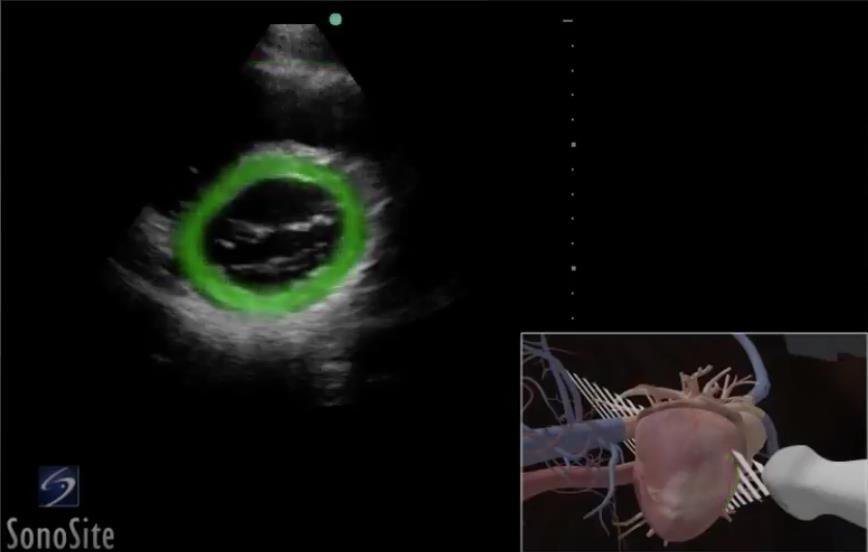

Heart Parasternal Short Axis (PSAX) Highlighted Myocardium 2 Image

Highlighted Area: Myocardium